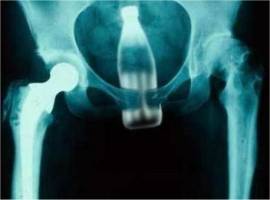

Einige kennt man bereits, andere sind dann schon ‚so was von …’. Wie auch immer. Ein Durchblättern bis zum ‚bitteren’ Ende sei meinerseits empfohlen, denn die minikleine Auswahl dieser Schnappschüsse und Momentaufnahmen aus dem Kuriositätenkabinett, die ich hier zeige, ist längst nicht der Höhepunkt: